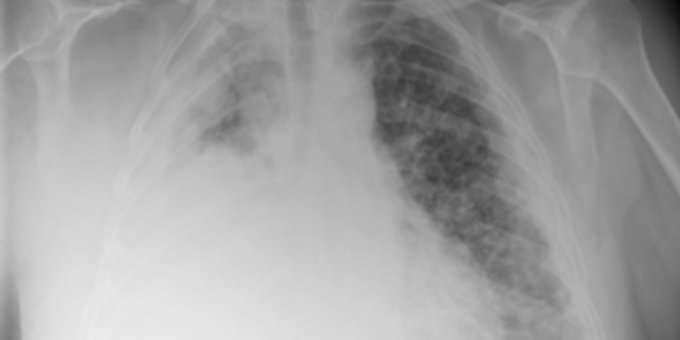

El mesotelioma es un tumor en el tejido que recubre los pulmones, el estómago, el corazón y otros órganos. Suele comenzar en los pulmones, pero también puede iniciar en otros órganos. Más aquí ow.ly/2wFG50AxPoS